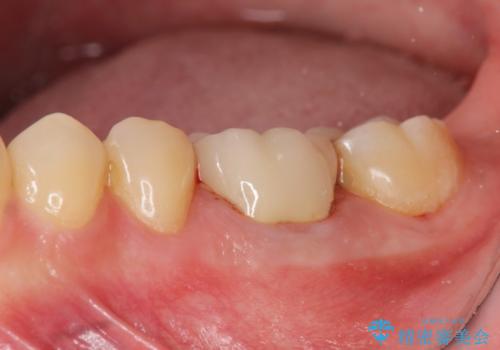

[フルジルコニアクラウン] 老朽化した銀歯を白く

セラミックインレー 下の一番奥歯 歯ぐきの厚みを減らしてぴったりに入れます(ディスタルウェッジ+骨外科)